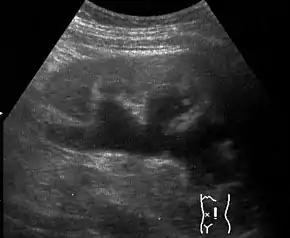

Massive hydronephrosis as marked by the arrow.- Renal ultrasonography of hydronephrosis[13]